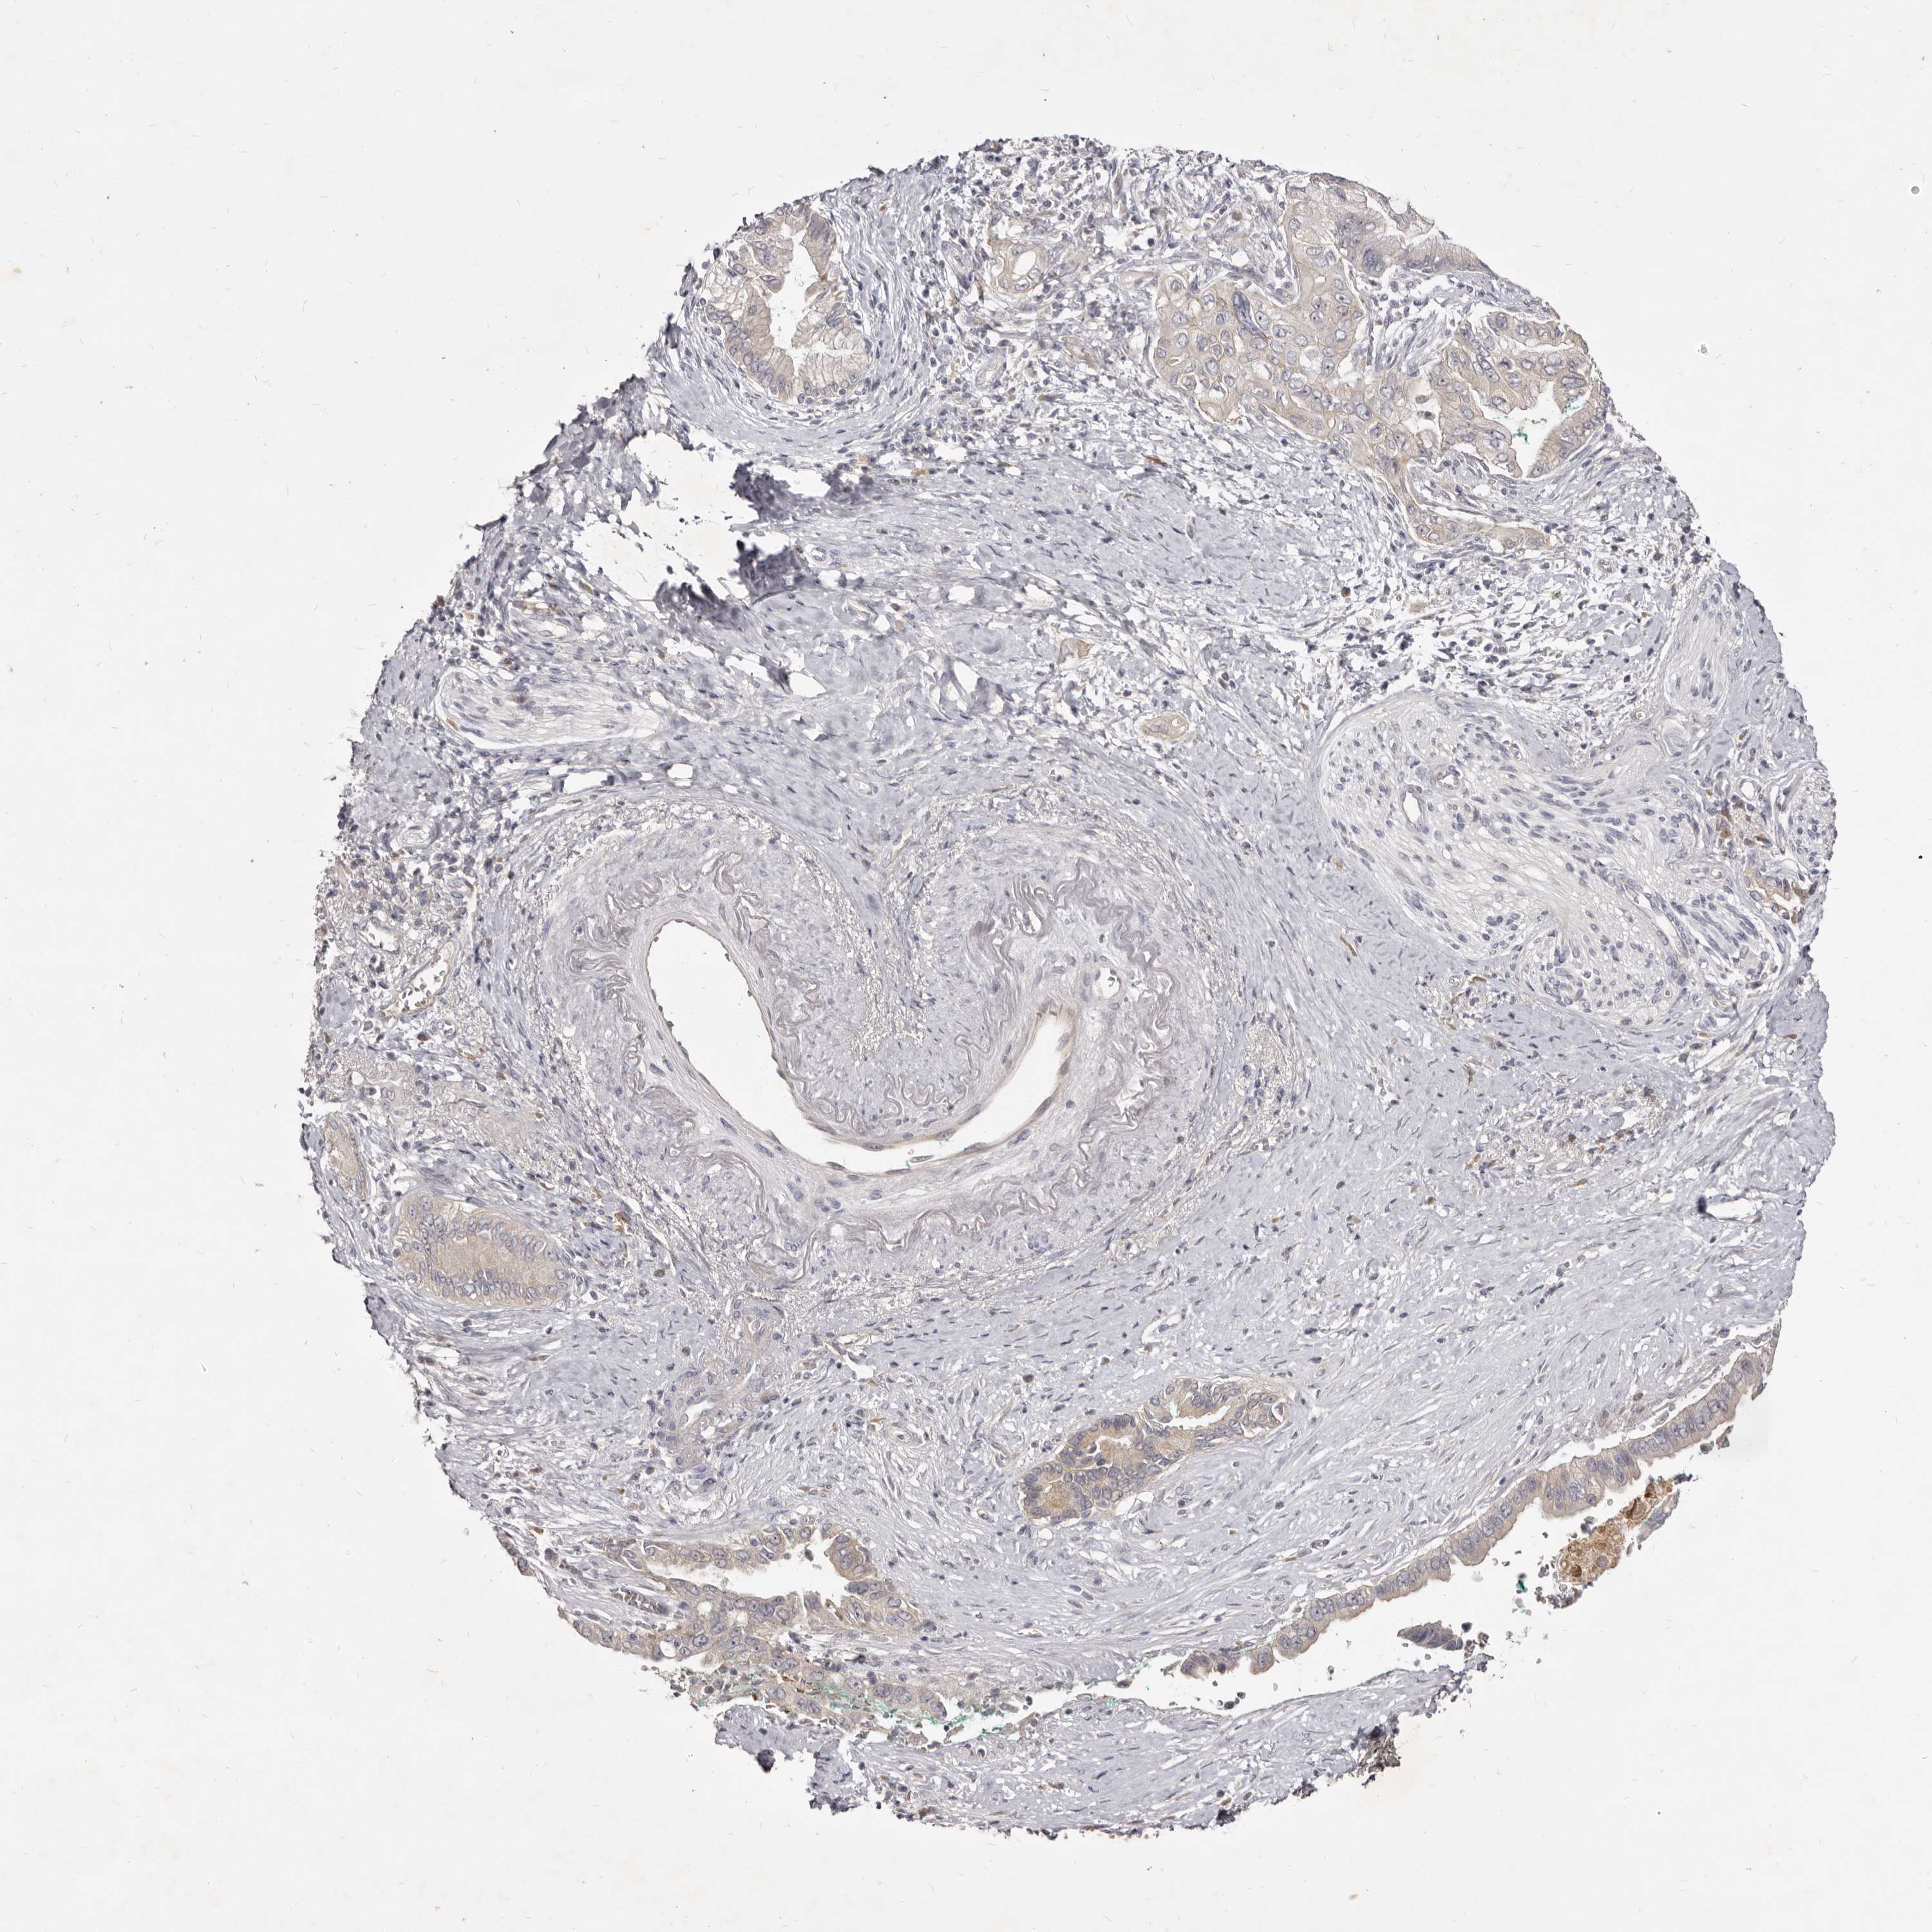

PANCREATIC CANCER - Protein expressioni

A mouse-over function shows sample information and annotation data. Click on an image to view it in a full screen mode. Samples can be filtered based on level of antibody staining by selecting one or several of the following categories: high, medium, low and not detected. The assay and annotation is described here.

Note that samples used for immunohistochemistry by the Human Protein Atlas do not correspond to samples in the TCGA dataset.

Antibody stainingi

Antibody staining in the annotated cell types in the current human tissue is reported as not detected, low, medium, or high, based on conventional immunohistochemistry profiling in selected tissues. This score is based on the combination of the staining intensity and fraction of stained cells.

Each image is clickable and will lead to virtual microscopy that enables deeper exploration of all samples and also displays staining intensity scores, fraction scores and subcellular localization as well as patient and tissue information for each sample.

Antibody HPA023081

Antibody HPA023103

Antibody HPA024795

Staining

High

Medium

Low

Not detected

Intensity

Strong

Moderate

Weak

Negative

Quantity

>75%

75%-25%

<25%

None

Location

Nuclear

Cytoplasmic/membranous

Cytoplasmic/membranous,nuclear

Adenocarcinoma, NOS